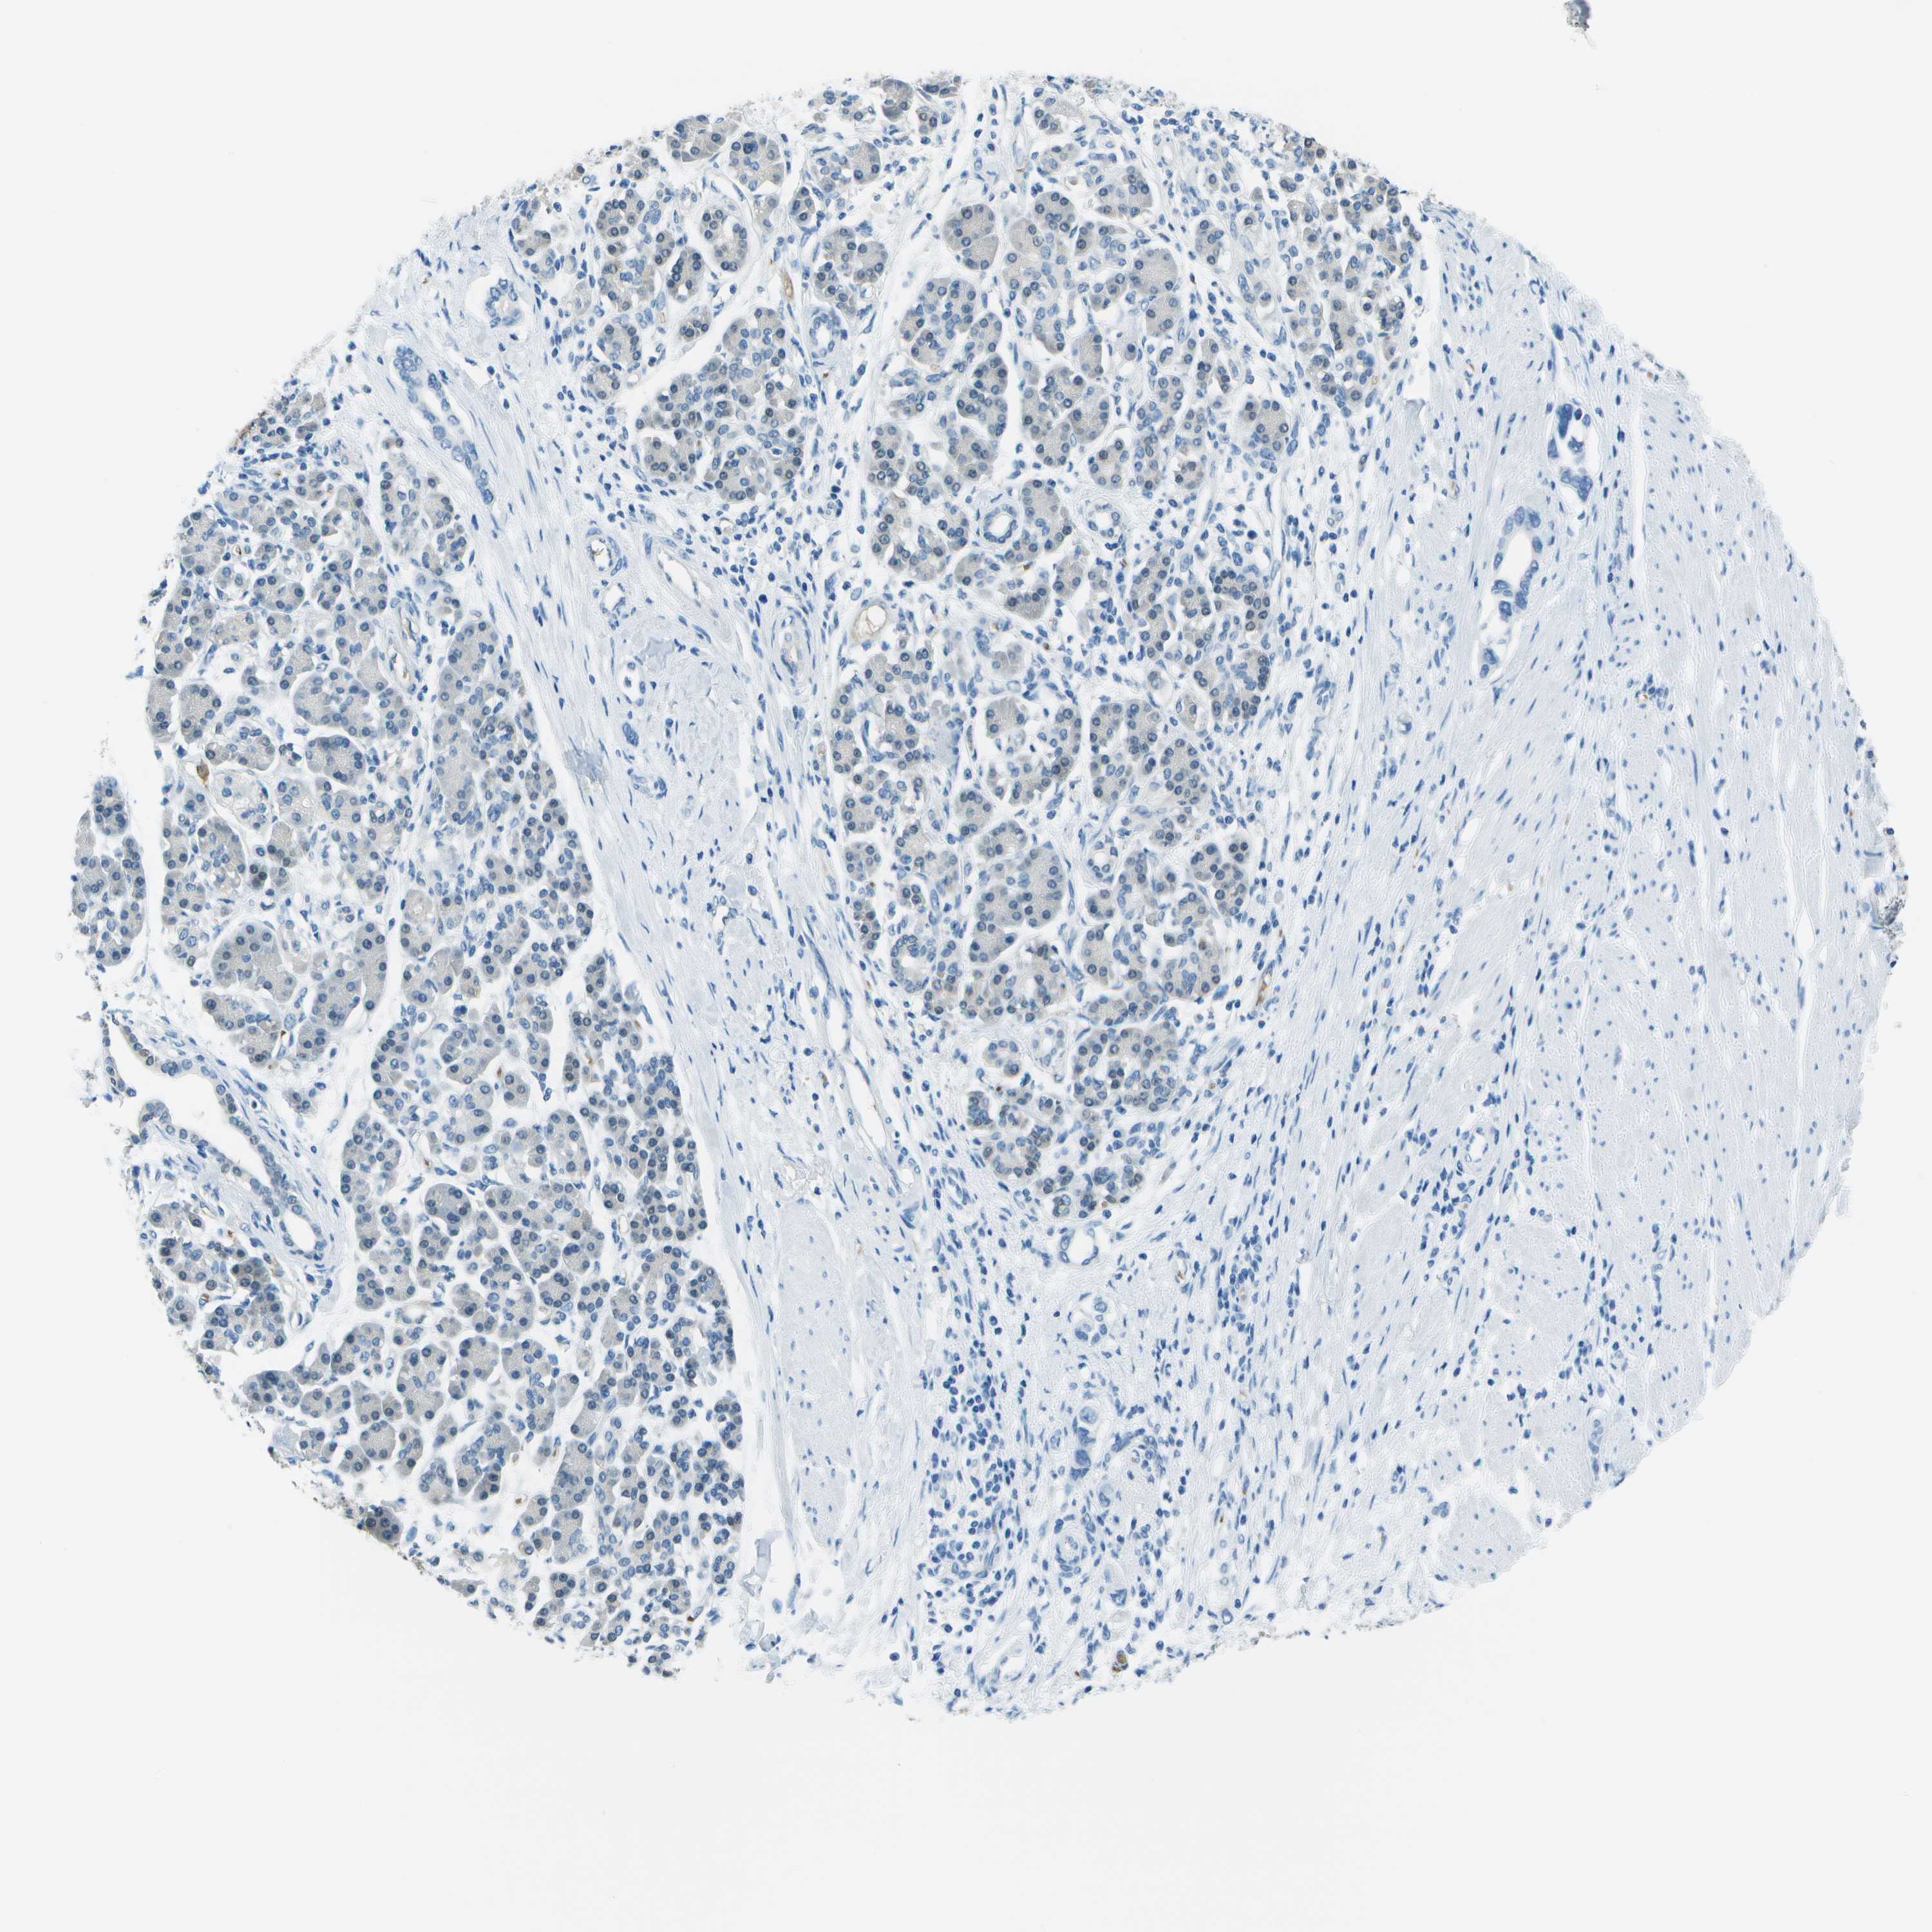

PANCREATIC CANCER - Protein expressioni

A mouse-over function shows sample information and annotation data. Click on an image to view it in a full screen mode. Samples can be filtered based on level of antibody staining by selecting one or several of the following categories: high, medium, low and not detected. The assay and annotation is described here.

Note that samples used for immunohistochemistry by the Human Protein Atlas do not correspond to samples in the TCGA dataset.

Antibody stainingi

Antibody staining in the annotated cell types in the current human tissue is reported as not detected, low, medium, or high, based on conventional immunohistochemistry profiling in selected tissues. This score is based on the combination of the staining intensity and fraction of stained cells.

Each image is clickable and will lead to virtual microscopy that enables deeper exploration of all samples and also displays staining intensity scores, fraction scores and subcellular localization as well as patient and tissue information for each sample.

Antibody HPA016646

Adenocarcinoma, NOS